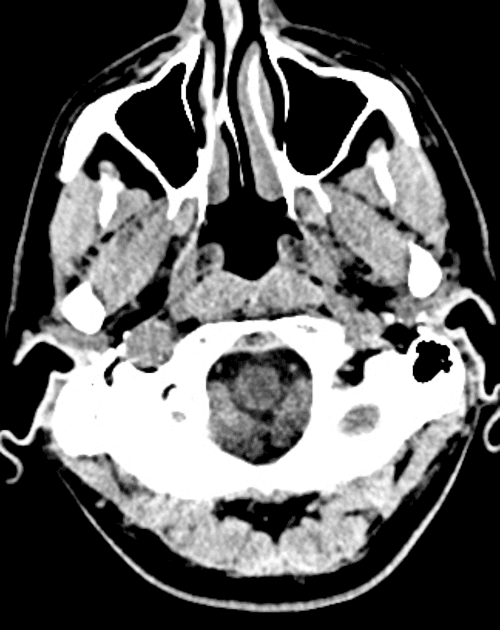

- Tổn thương dạng khối nang ở thùy thái dương trước bên phải (right anterior temporal lobe cystic mass lesion) được ghi nhận, trên cộng hưởng từ cho thấy tín hiệu giảm ở chuỗi xung T1, tăng tín hiệu ở T2, viền giảm tín hiệu trên mọi chuỗi xung.

- Tổn thương được bao quanh bởi phù vận mạch (vasogenic edema), gây xóa (effacement) các rãnh vỏ não tương ứng và chèn ép nhẹ sừng thái dương của não thất bên phải.

- Ghi nhận dày lên và ngấm thuốc của màng não (meninges) kế cận.

- Xương sọ đáy cũng bất thường: giảm tín hiệu trên T1, tăng tín hiệu trên T2, ngấm thuốc không đồng nhất, gợi ý viêm xương (osteomyelitis).

- Tổn thương lan rộng vào khoảng gian súc bên phải (right masticator space), các cơ cánh, và hõm dưới thái dương phải (right infra-temporal fossa), với các dấu hiệu viêm: tăng tín hiệu T2 và ngấm thuốc không đồng nhất sau tiêm.

- Các hốc khí tai giữa và xương chũm bị tràn dịch.